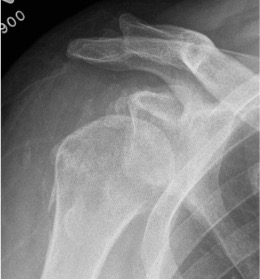

Xray

Signs of chronic shoulder dislocation